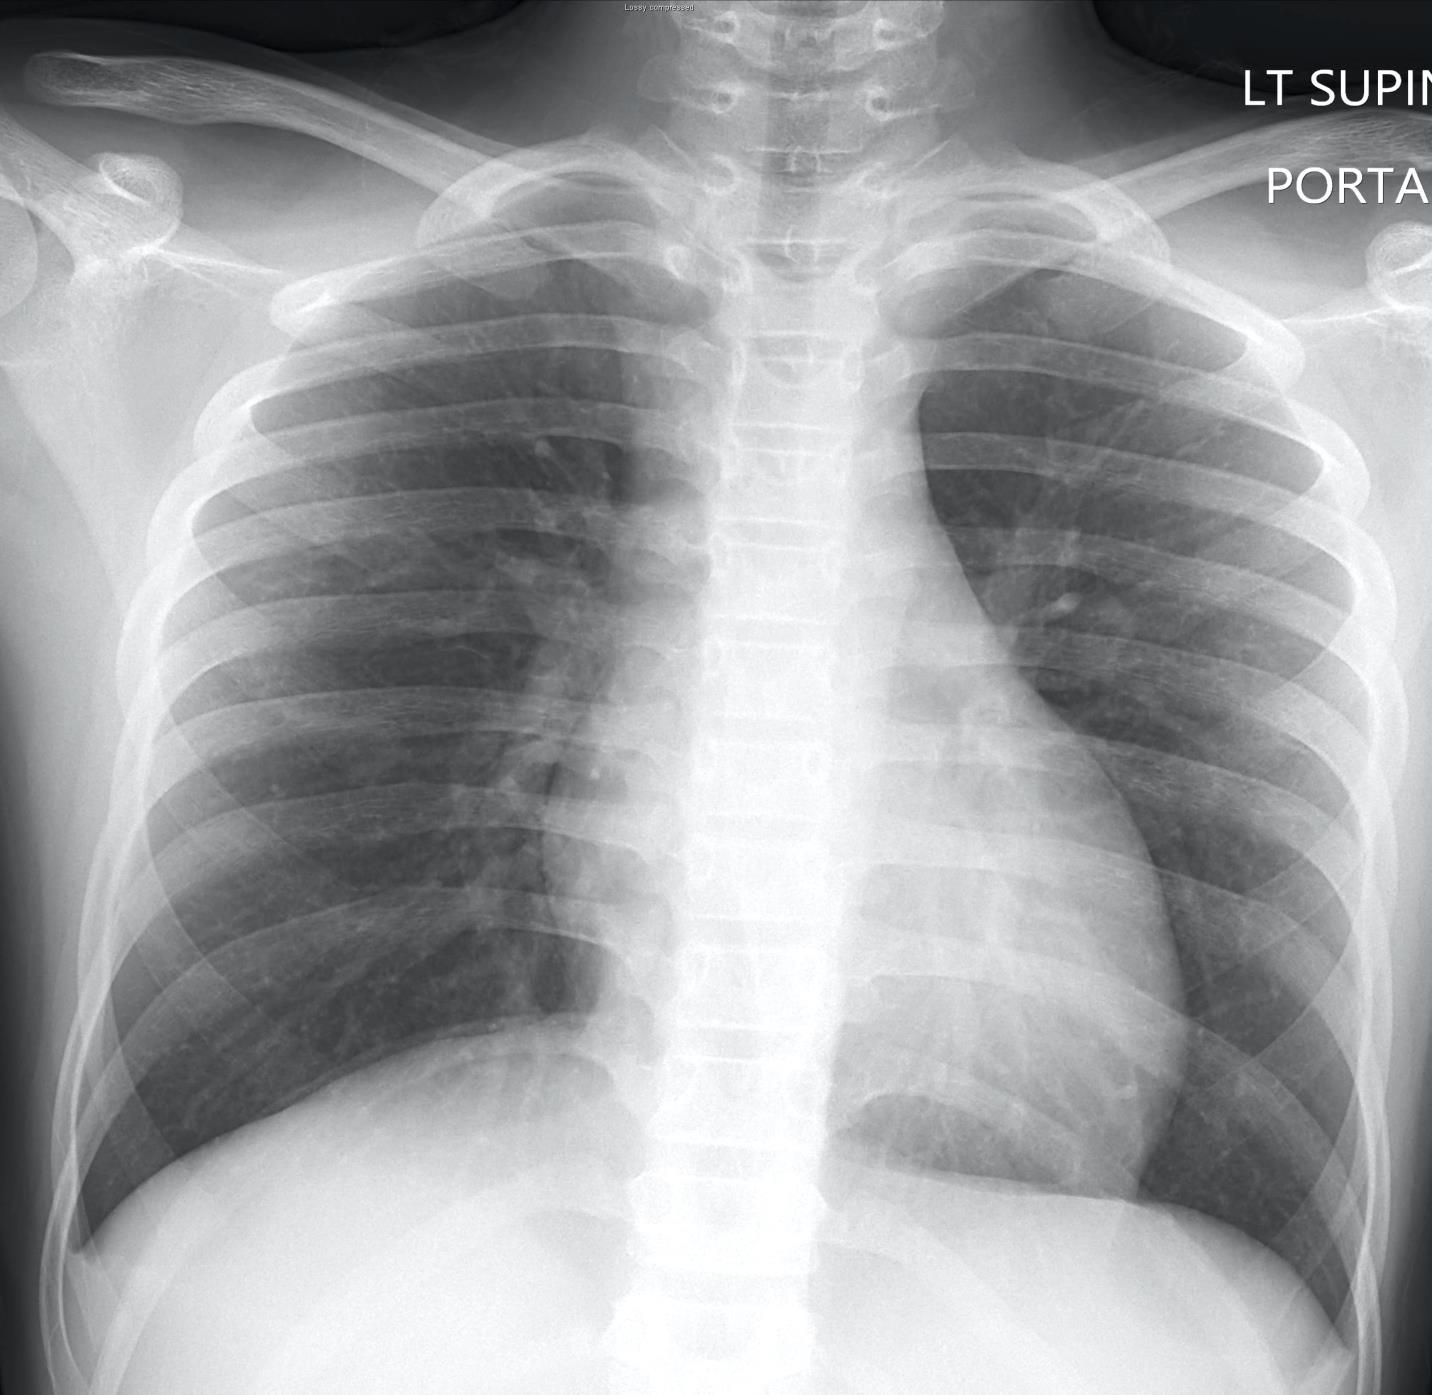

Imaging of Covid 19 infection in children CXR 8 38% 3% 51% 8%

Consolidation 35%

Collapse 3%

PeriBronchial thickening

51%

Hyperexpansion 7%

Effusion 4%

Imaging of Covid 19 infection in children CXR 9 C O V I D

Birmingham

Covid 19 CXR Imaging of Covid 19 infection in children